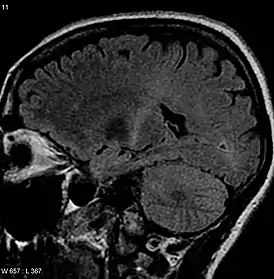

- МРТ головного и спинного мозга

- выявление отмирания пирамидных путей на МРТ